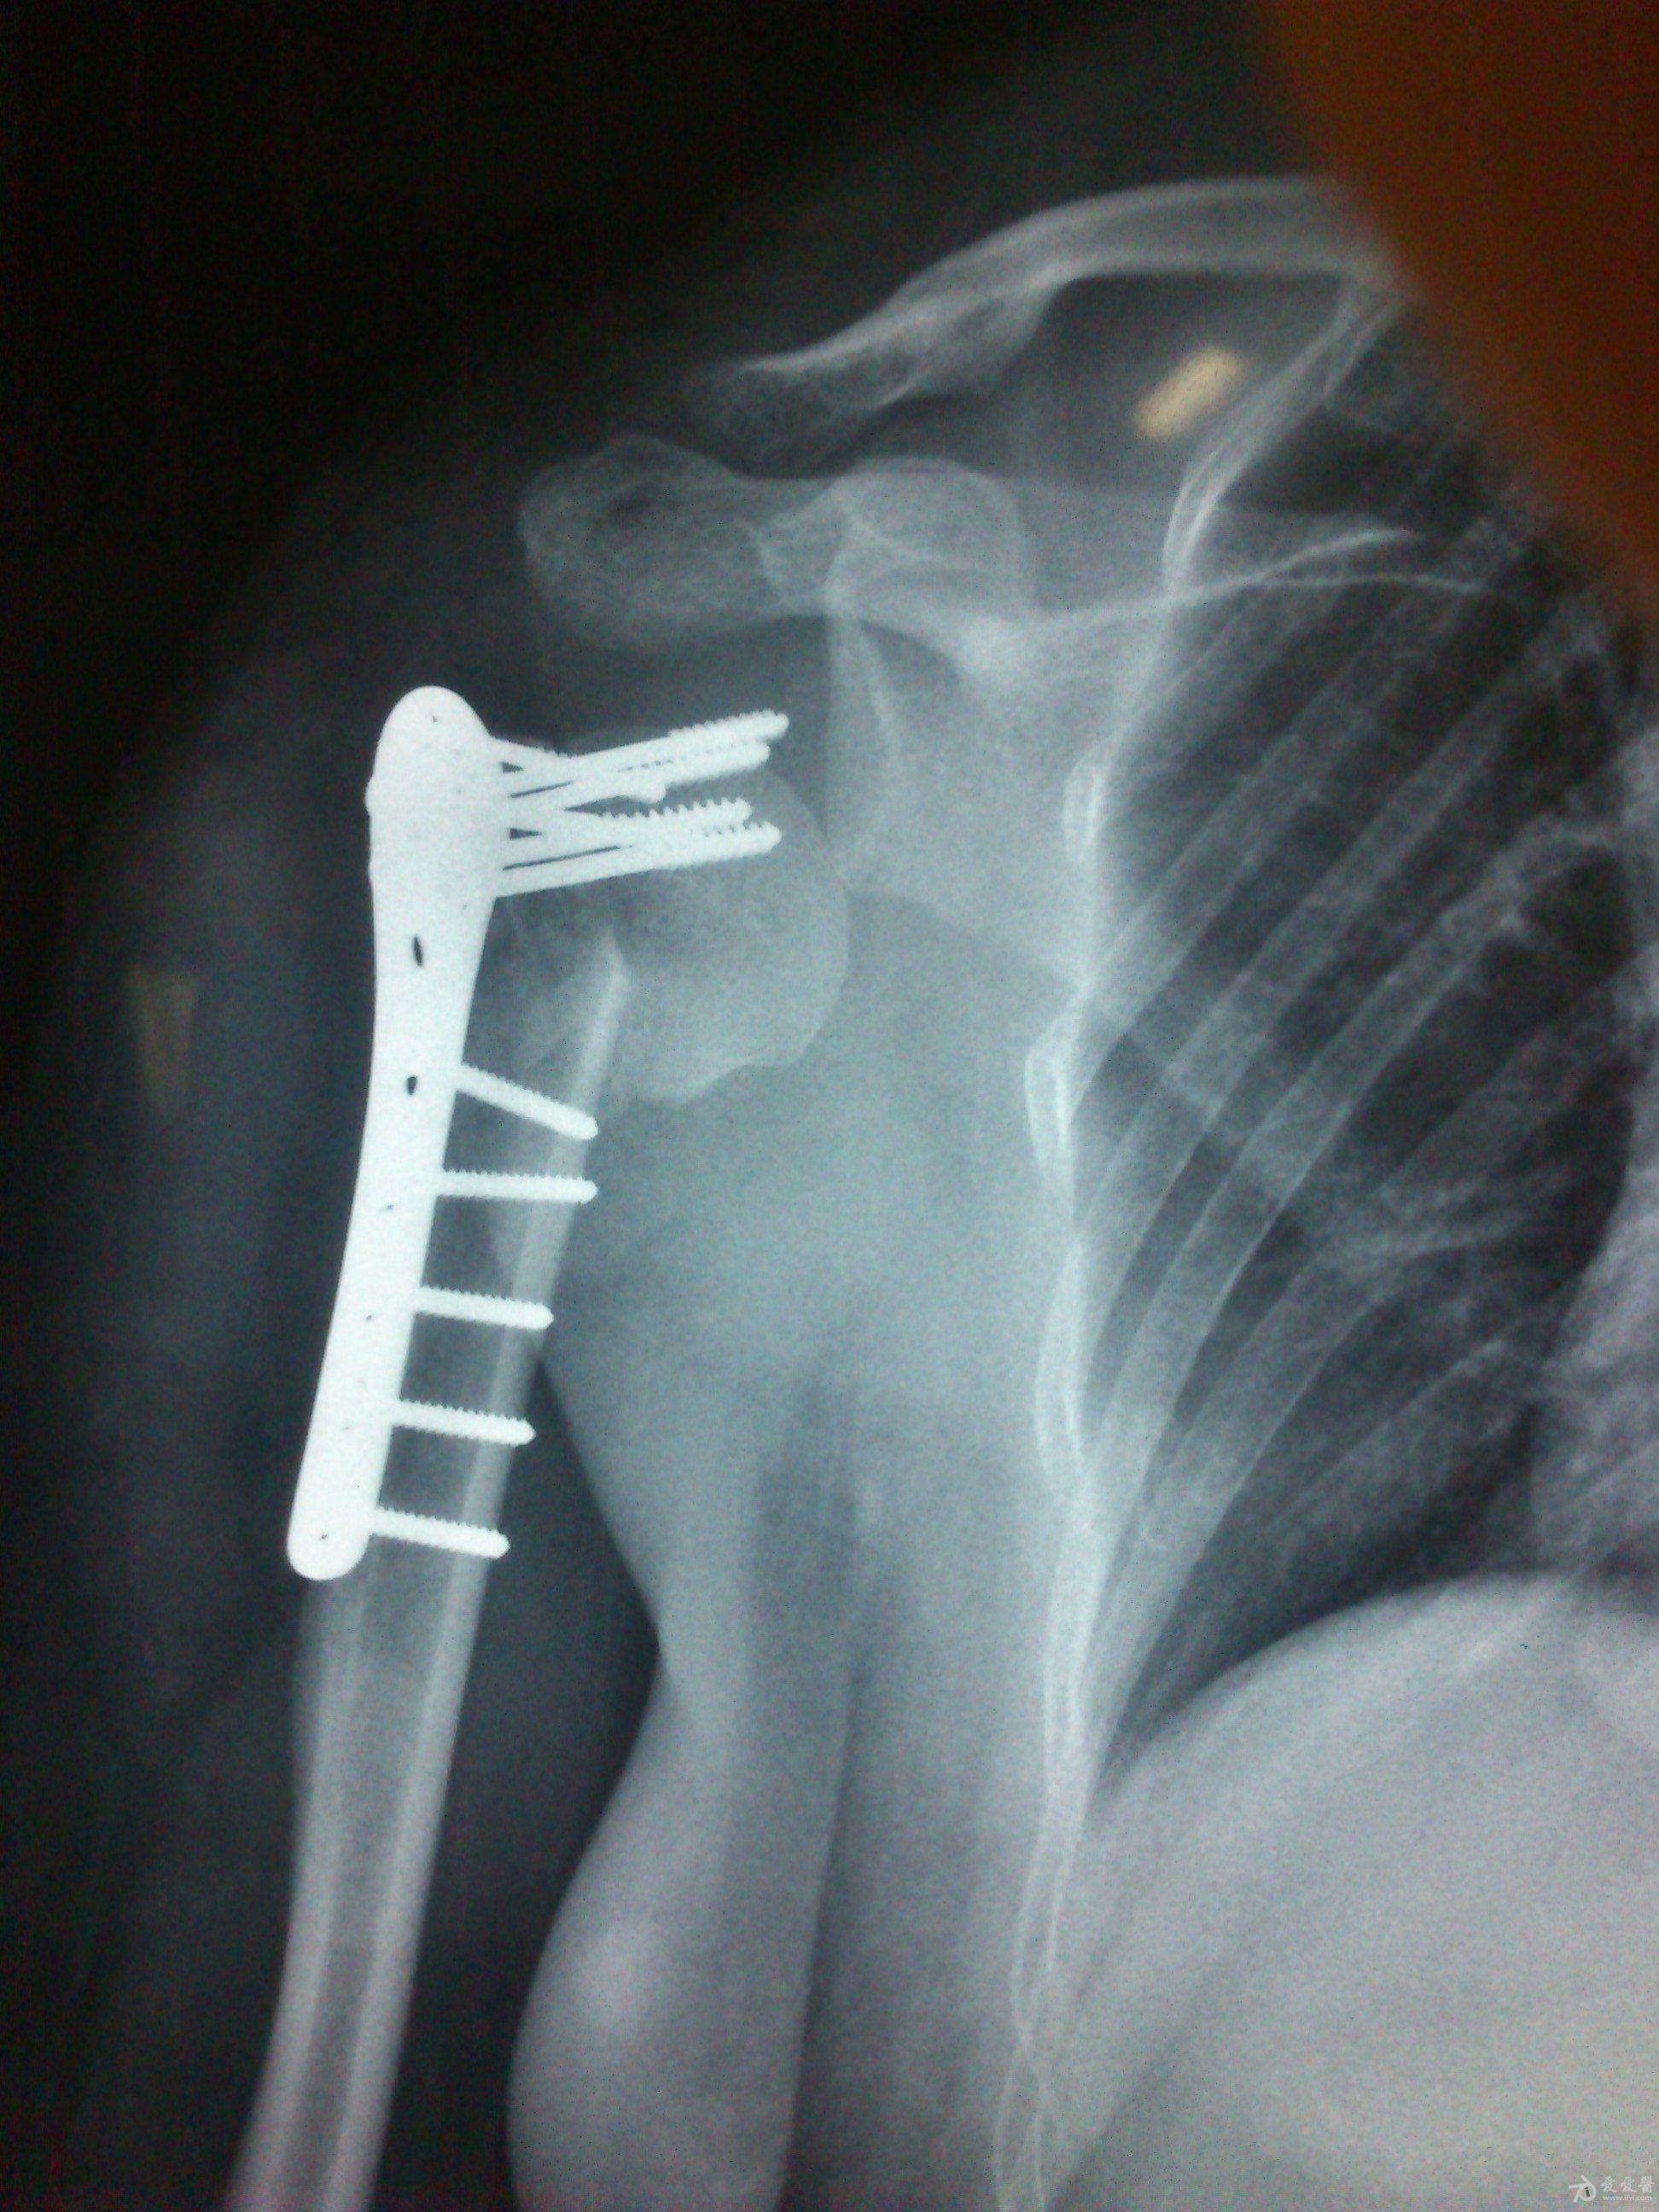

病史特点及病情摘要:1、患者女性,51岁。2、患者自诉入院前1年余因右肱骨外科颈骨折在外院行切开复位内固定术,术后右肩关节疼痛、活动受限,一直未予处理,今为明确诊治入院。患者精神、食欲、睡眠尚可。3、既往史、个人史、家族史无特殊。4、入院查体:生命征平稳,心肺腹检查未见异常,NS(-)。专科情况:右上臂近端内侧见一约15cm手术切口疤痕,愈合佳,右肩关节能外展20度,前屈、后伸及旋前、旋后功能障碍,余关节活动好。舌质红,苔薄白,脉实。5、辅助检查:右肩关节正侧位片:右肱骨外科颈骨折内固定术后再骨折伴右肩关节脱位。

诊断:右肱骨外科颈骨折内固定术后再骨折伴右肩关节脱位

院外术后

同意楼主观点,患者第一次手术复位欠佳,但可勉强接受。但钉子穿出,是手术后肩关节疼痛的主要原因,现在看骨折已愈合,头无明显头坏死迹象,只需取出内固定,麻醉下活动肩关节,使肩关节活动度改善,术后加强功能锻炼,应该恢复不错。